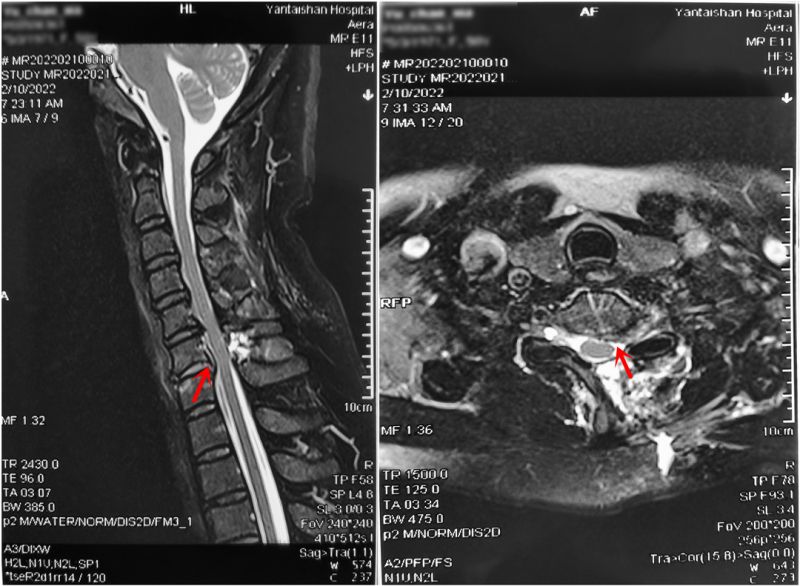

术前MRI示C6/7椎间盘突出并颈髓明显受压。

术后MRI示C6/7水平突出的间盘完全摘除,颈髓减压充分。